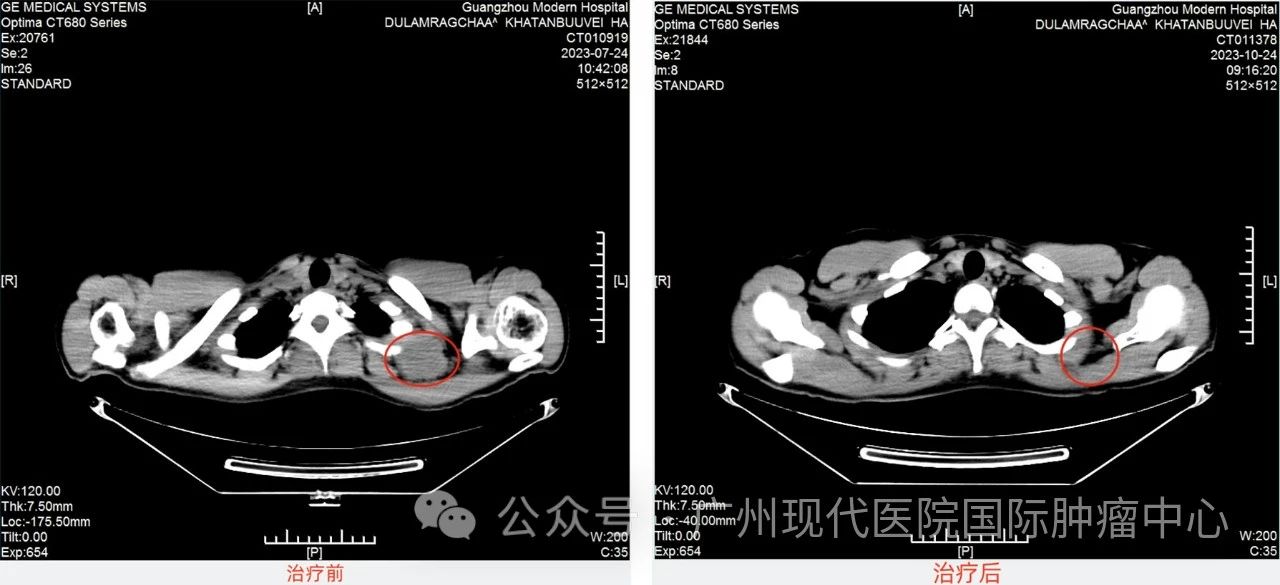

哈腾的主治医生胡医生表示:尤文氏肉瘤,是一种多发于儿童和青少年的骨肿瘤,主要发生于骨盆,股骨,胫骨、肱骨和肋骨,也常出现在骨骼临近的软组织中。是恶性程度较高的一种肿瘤,发展进程较快。哈腾的检查结果也证明了这一点:哈腾的肿瘤在快速生长,由原来的3cm长到了5cm,幸运的是没有远处转移。根据哈腾的病情与意愿,医院制定了“微创介入+根治手术”的治疗方案。微创介入治疗是在医学影像设备引导下进行穿刺,将特制导管等精密器械通过动脉插入病灶血管通道,用特殊物质栓塞、堵闭血管,将抗癌药物和栓塞剂有机结合,再一起注入靶动脉,既阻断供血,同时药物停留于肿瘤区,“饿死、毒死”肿瘤。相对于传统的化疗,介入治疗毒副作用更低,对身体伤害更小。哈腾说:“介入手术过程中没有不适,因为治疗前医生有详细说明手术情况,也不紧张,治疗后副作用没有很大,第一次介入的时候偶尔有疼痛,后面几次感觉就好了很多,而且我有明显感受到肿瘤缩小了,我很开心。”经过4次介入治疗后,再次检查肿瘤已缩小至2cm, 相较治疗前缩小了一半多。10月28日,哈腾进行了手术根治术,切除了左侧肩胛骨尤文氏肉瘤和左侧颈部淋巴结。术后病理显示:肩胛骨部组织,颈部淋巴未见肿瘤残留,肿瘤疗效评估:完全缓解。【左图为7月肩胛部位CT:肿瘤大小范围约46mm×79mm已侵犯肩胛骨】

【左图为7月颈部淋巴部位CT:肿瘤大小直径约50mm】哈腾的主治医生胡医生说:“哈腾是个勇敢的孩子,在治疗期间,情绪一直稳定,取得初步胜利我们都为他高兴,我们会一起陪伴他战胜癌症。他的人生还有无限可能,我们祝福他。”